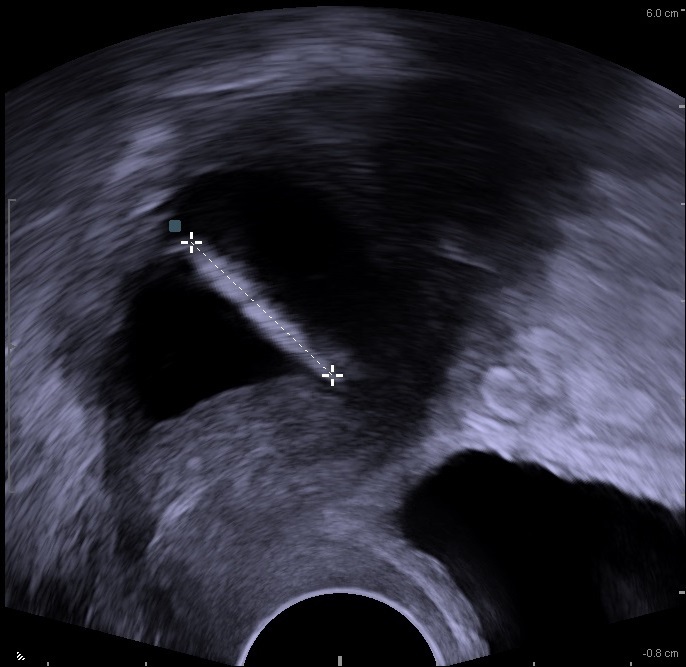

Σπιράλ χαλκού που διαπέρασε την μήτρα όπως φαίνεται στους υπερήχους

Οι κίνδυνοι που σχετίζονται με οποιονδήποτε από τους δύο τύπους σπιράλ περιλαμβάνουν:

- Διάτρηση (τρύπημα ή διείσδυση) του σπιράλ στην μήτρα ή σε ένα κοντινό όργανο η οποία μπορεί να προκαλέσει σοβαρή αιμορραγία.

Αυτές οι παρενέργειες είναι σπάνιες, αλλά μια μελέτη που χρηματοδοτήθηκε από τον FDA και δημοσιεύτηκε στο Lancet το 2022 κατέληξε ότι η διάτρηση ήταν πολύ πιο πιθανό να συμβεί από ό,τι είχε υποτεθεί προηγουμένως. Οι κίνδυνοι ήταν υψηλότεροι για τις γυναίκες που είχαν τοποθετήσει σπιράλ τους πρώτους μήνες μετά τον τοκετό.